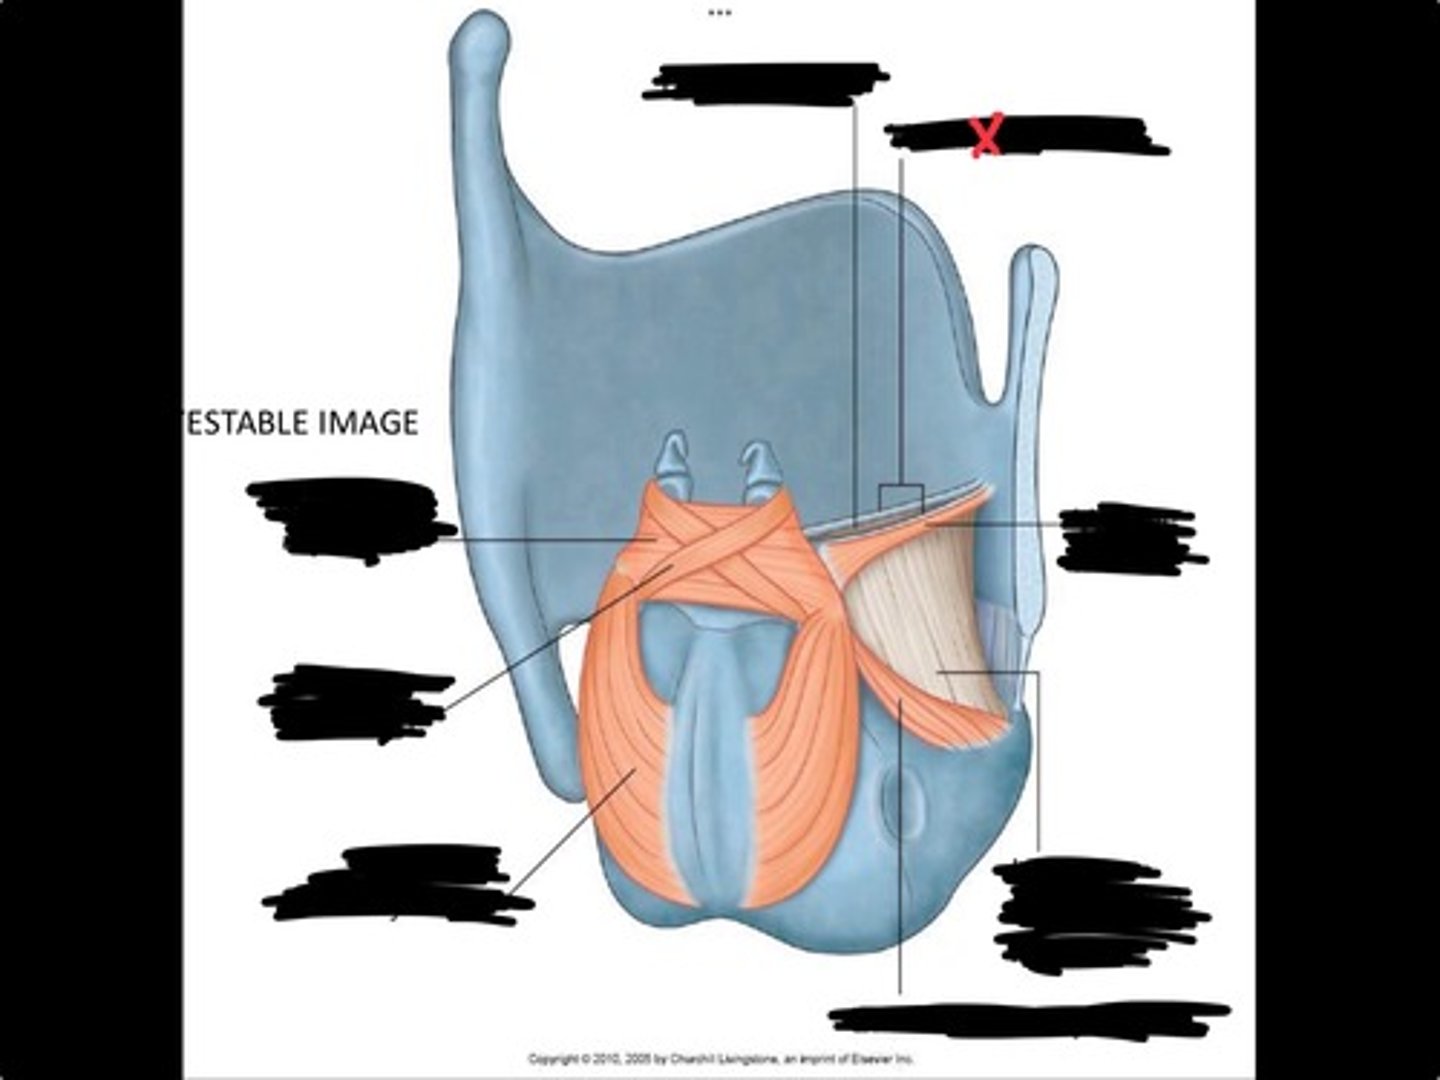

Vocal process of arytenoid

Conus elasticus

Vestibular ligament

Quadrangular membrane

Epiglottis

vocal ligament

Aryepiglottic ligament

Muscular process of arytenoid

Corniculate cartilage

Posterior crico arytenoid

oblique arytenoid

transverse artyenoid

Rima glottidis

Vocal ligament

Vocalis muscle

Lateral cricothyroid ligament

Lateral cricoartenoid